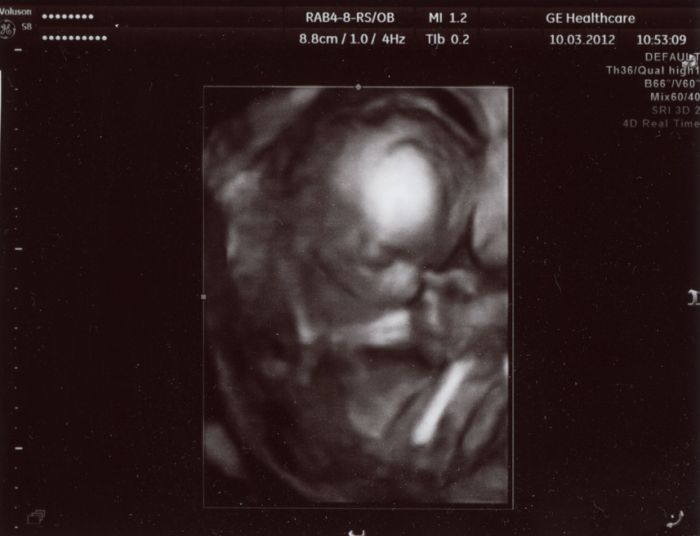

Tady je pár foteček. Video dostanu za 2 týdny až tam půjdu na kontrolu. Ten jeho přístroj mu to nedovede hned zpracovat, tak nám to video nemohl hned dát.